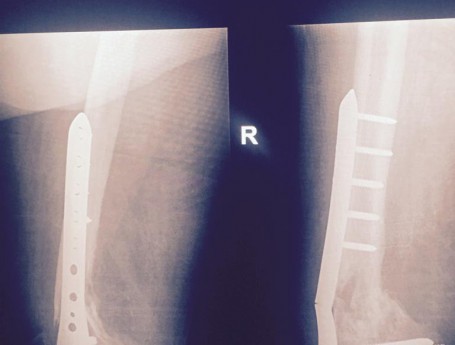

Total Knee Arthroplasty After a non-union